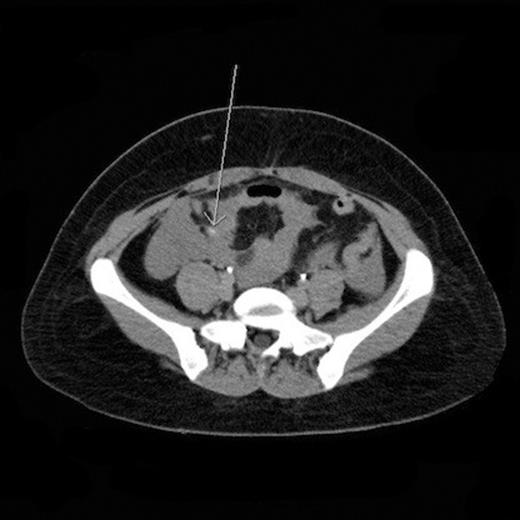

A computed tomography angiogram (CTA) was performed with arterial and venous phase contrast, and active arterial extravasation along the mesentery within the right lower quadrant was identified (Fig. 1). The spleen was also mildly enlarged at 15 cm in length. At that time, her temperature was 99.2°F, heart rate was 110-120 bpm, respiratory rate was 20/minute, blood pressure was 90/67 mmHg, and oxygen saturation was 98% on two liters/minute nasal cannula oxygen. Pertinent laboratory values are as follows: white blood cell count 8.3 x 103/µL, hemoglobin 9.8 g/dL, hematocrit 29.7%, platelets 135 x 103/µL, creatinine 0.91 mg/dL, INR 1.1, and lactic acid 2.7 mmol/L.

CT angiogram of the abdomen and pelvis revealed active extravasation within the right lower quadrant